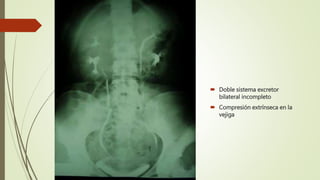

 Doble sistema excretor

bilateral incompleto

 Compresión extrínseca en la

vejiga

 Doble sistemaexcretor bilateral incompleto  Compresión extrínseca en la vejiga